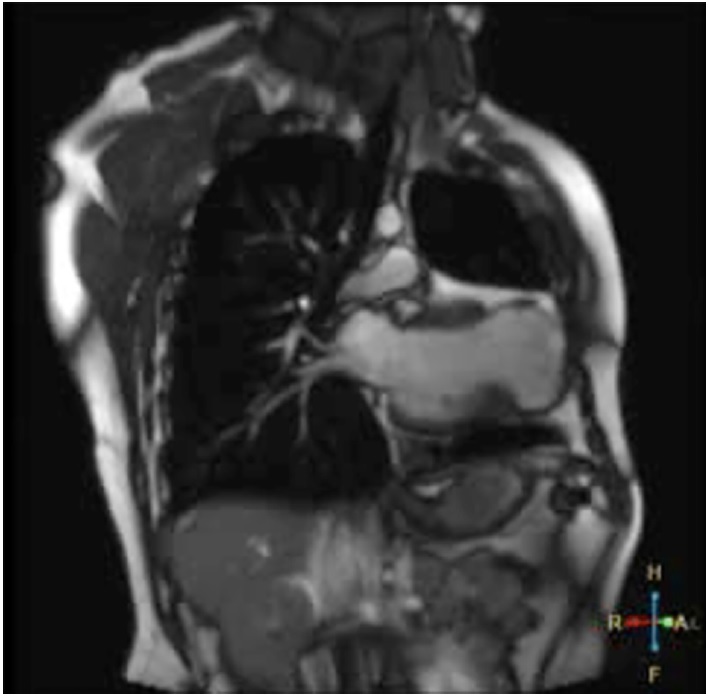

Presentamos un paciente de sexo masculino de 30 años, con antecedentes de miocardiopatía dilatada isquémico-necrótica no ateroesclerótica, con fracción de eyección ventricular izquierda (FEVI) reducida (35%) y aneurisma ventricular (Figura 1) por lesión iatrogénica, extrínseca, tras la sutura de la arteria descendente anterior, luego de una herida de arma de fuego y cirugía de urgencia. Evoluciona posteriormente con varias internaciones por episodios recurrentes de taquicardia ventricular monomorfa sostenida (TVMS) (Figura 2a) por lo que se decide colocación de un dispositivo cardiodefibrilador implantable (CDI) y ablación del sustrato, con evolución favorable.

Fig. 1 Corte coronal de resonancia magnética en secuencia T2 donde se evidencia dilatación ventricular izquierda, la presencia de saco aneurismático apical, adelgazamiento miocárdico y señal de baja intensidad.